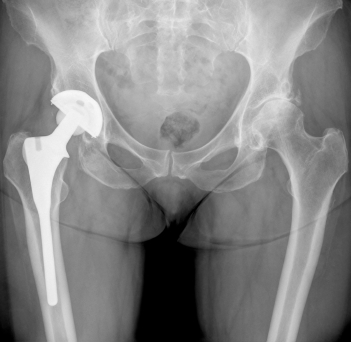

- Loosening of the implant: Loosening of implant components is one of the most serious complications, since it is a strong indicator of whether a patient will require revision surgery. Early implant loosening can be diagnosed through a series of X-rays, taken at different times to determine component positions. Implant loosening may be linked to other issues including metallosis and bone loss.